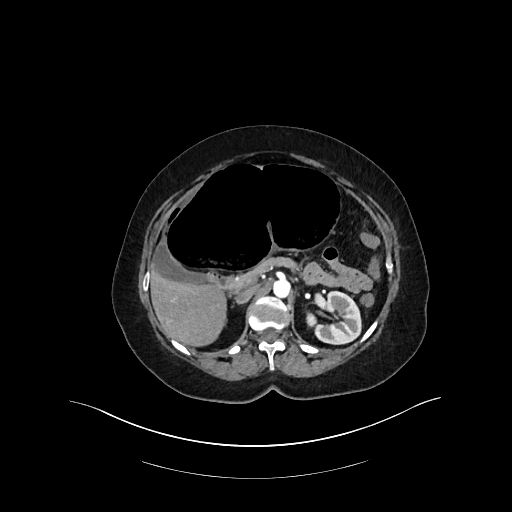

Une patiente de 59 ans, avec antécédents de lithiases vésiculaires, se présente aux urgences pour une douleur abdominale diffuse à type de colique, d'apparition brutale depuis la veille au soir. La douleur est d'intensité 8/10, sans position antalgique ni caractère transfixiant. La patiente signale que ces douleurs sont similaires à ses épisodes antérieurs de migration lithiasique biliaire. Le tableau clinique est également marqué par des nausées, six vomissements liquidiens et un vomissement biliaire à l'admission. La patiente note une inappétence ainsi qu'un épisode de selles liquides la veille. Ses antécédents chirurgicaux se limitent à une césarienne. A l'examen, la patiente est très inconfortable sans position antalgique, et afébrile (36,7°C). Les constantes vitales sont stables (TA 100/71 mm Hg, FC 83 bpm, FR 16 cycles/min, SpO2 95%). L'abdomen est souple, sensible en sus-pubien et épigastrique avec masse palpable sans défense ni détente. Les signes de Murphy et du psoas sont négatifs. Le bilan biologique révèle une légère hyperleucocytose (11,4 G/L) et une CRP à 6,8 mg/L, avec tests hépatiques normaux et des lactates à 1,2 mmol/L.